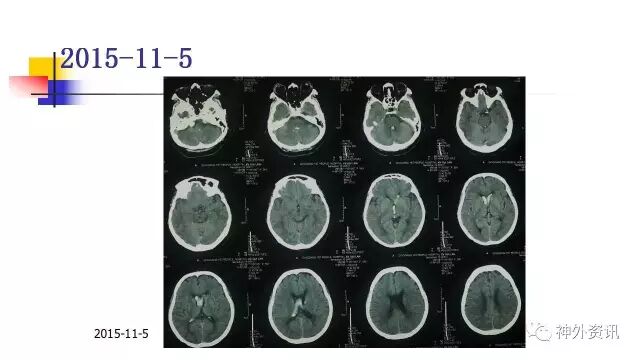

手术过程